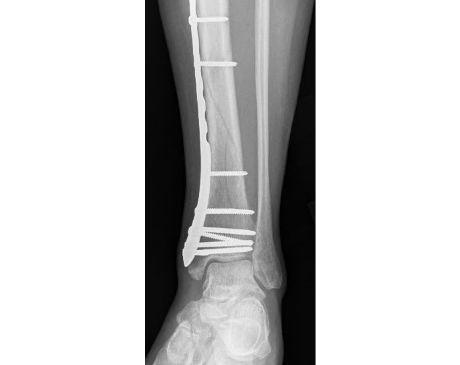

I was hit by car, had a compound fracture with a bone sticking out of my left foot. Broken tibia and fibia?. Screwed plate and bones back together. I am healing fine, next visit 3/26 to remove stiches. I seem to have total function of foot. Still have 2 more weeks of not using leg, but very hopeful.